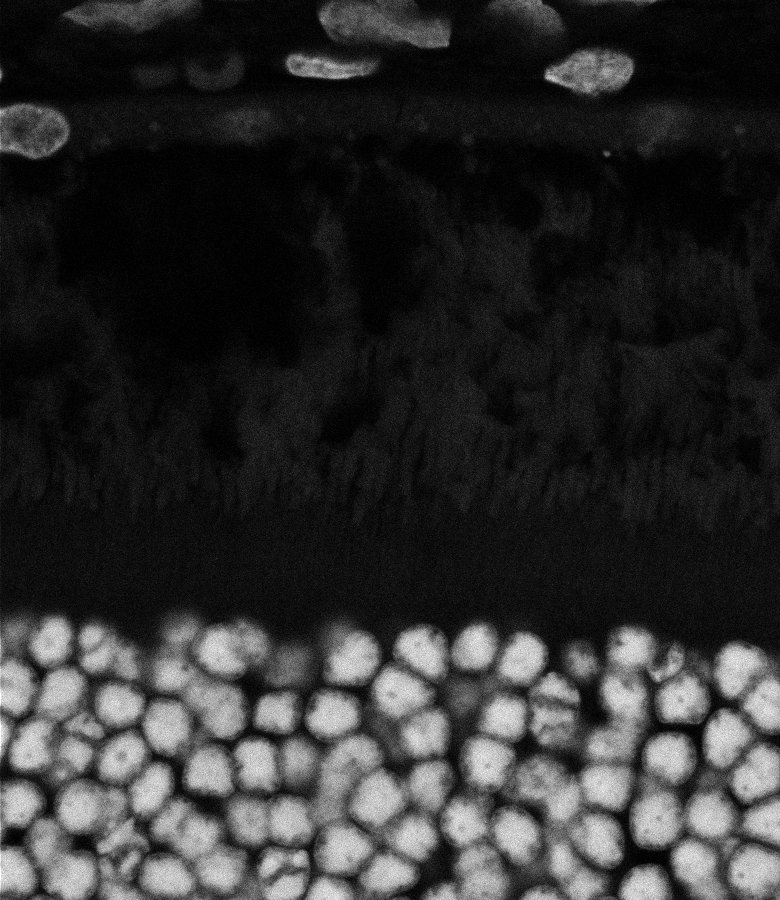

Healthy Retina

Unhealthy Retina

Healthy Choroid

Unhealthy Choroid